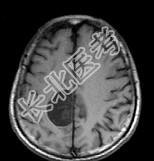

- 单项选择题男,68岁, 头痛头昏、左侧肢体肌力减退3个月余,请根据所提供图像, 选择最可能的诊断是 ( )

A、(右顶叶镰旁)血管外皮瘤

B、(右顶叶镰旁)转移瘤

C、(右顶叶镰旁)脑膜瘤(血管瘤型)

D、(右顶叶镰旁)胶质瘤

E、(右顶叶镰旁)恶性脑膜瘤